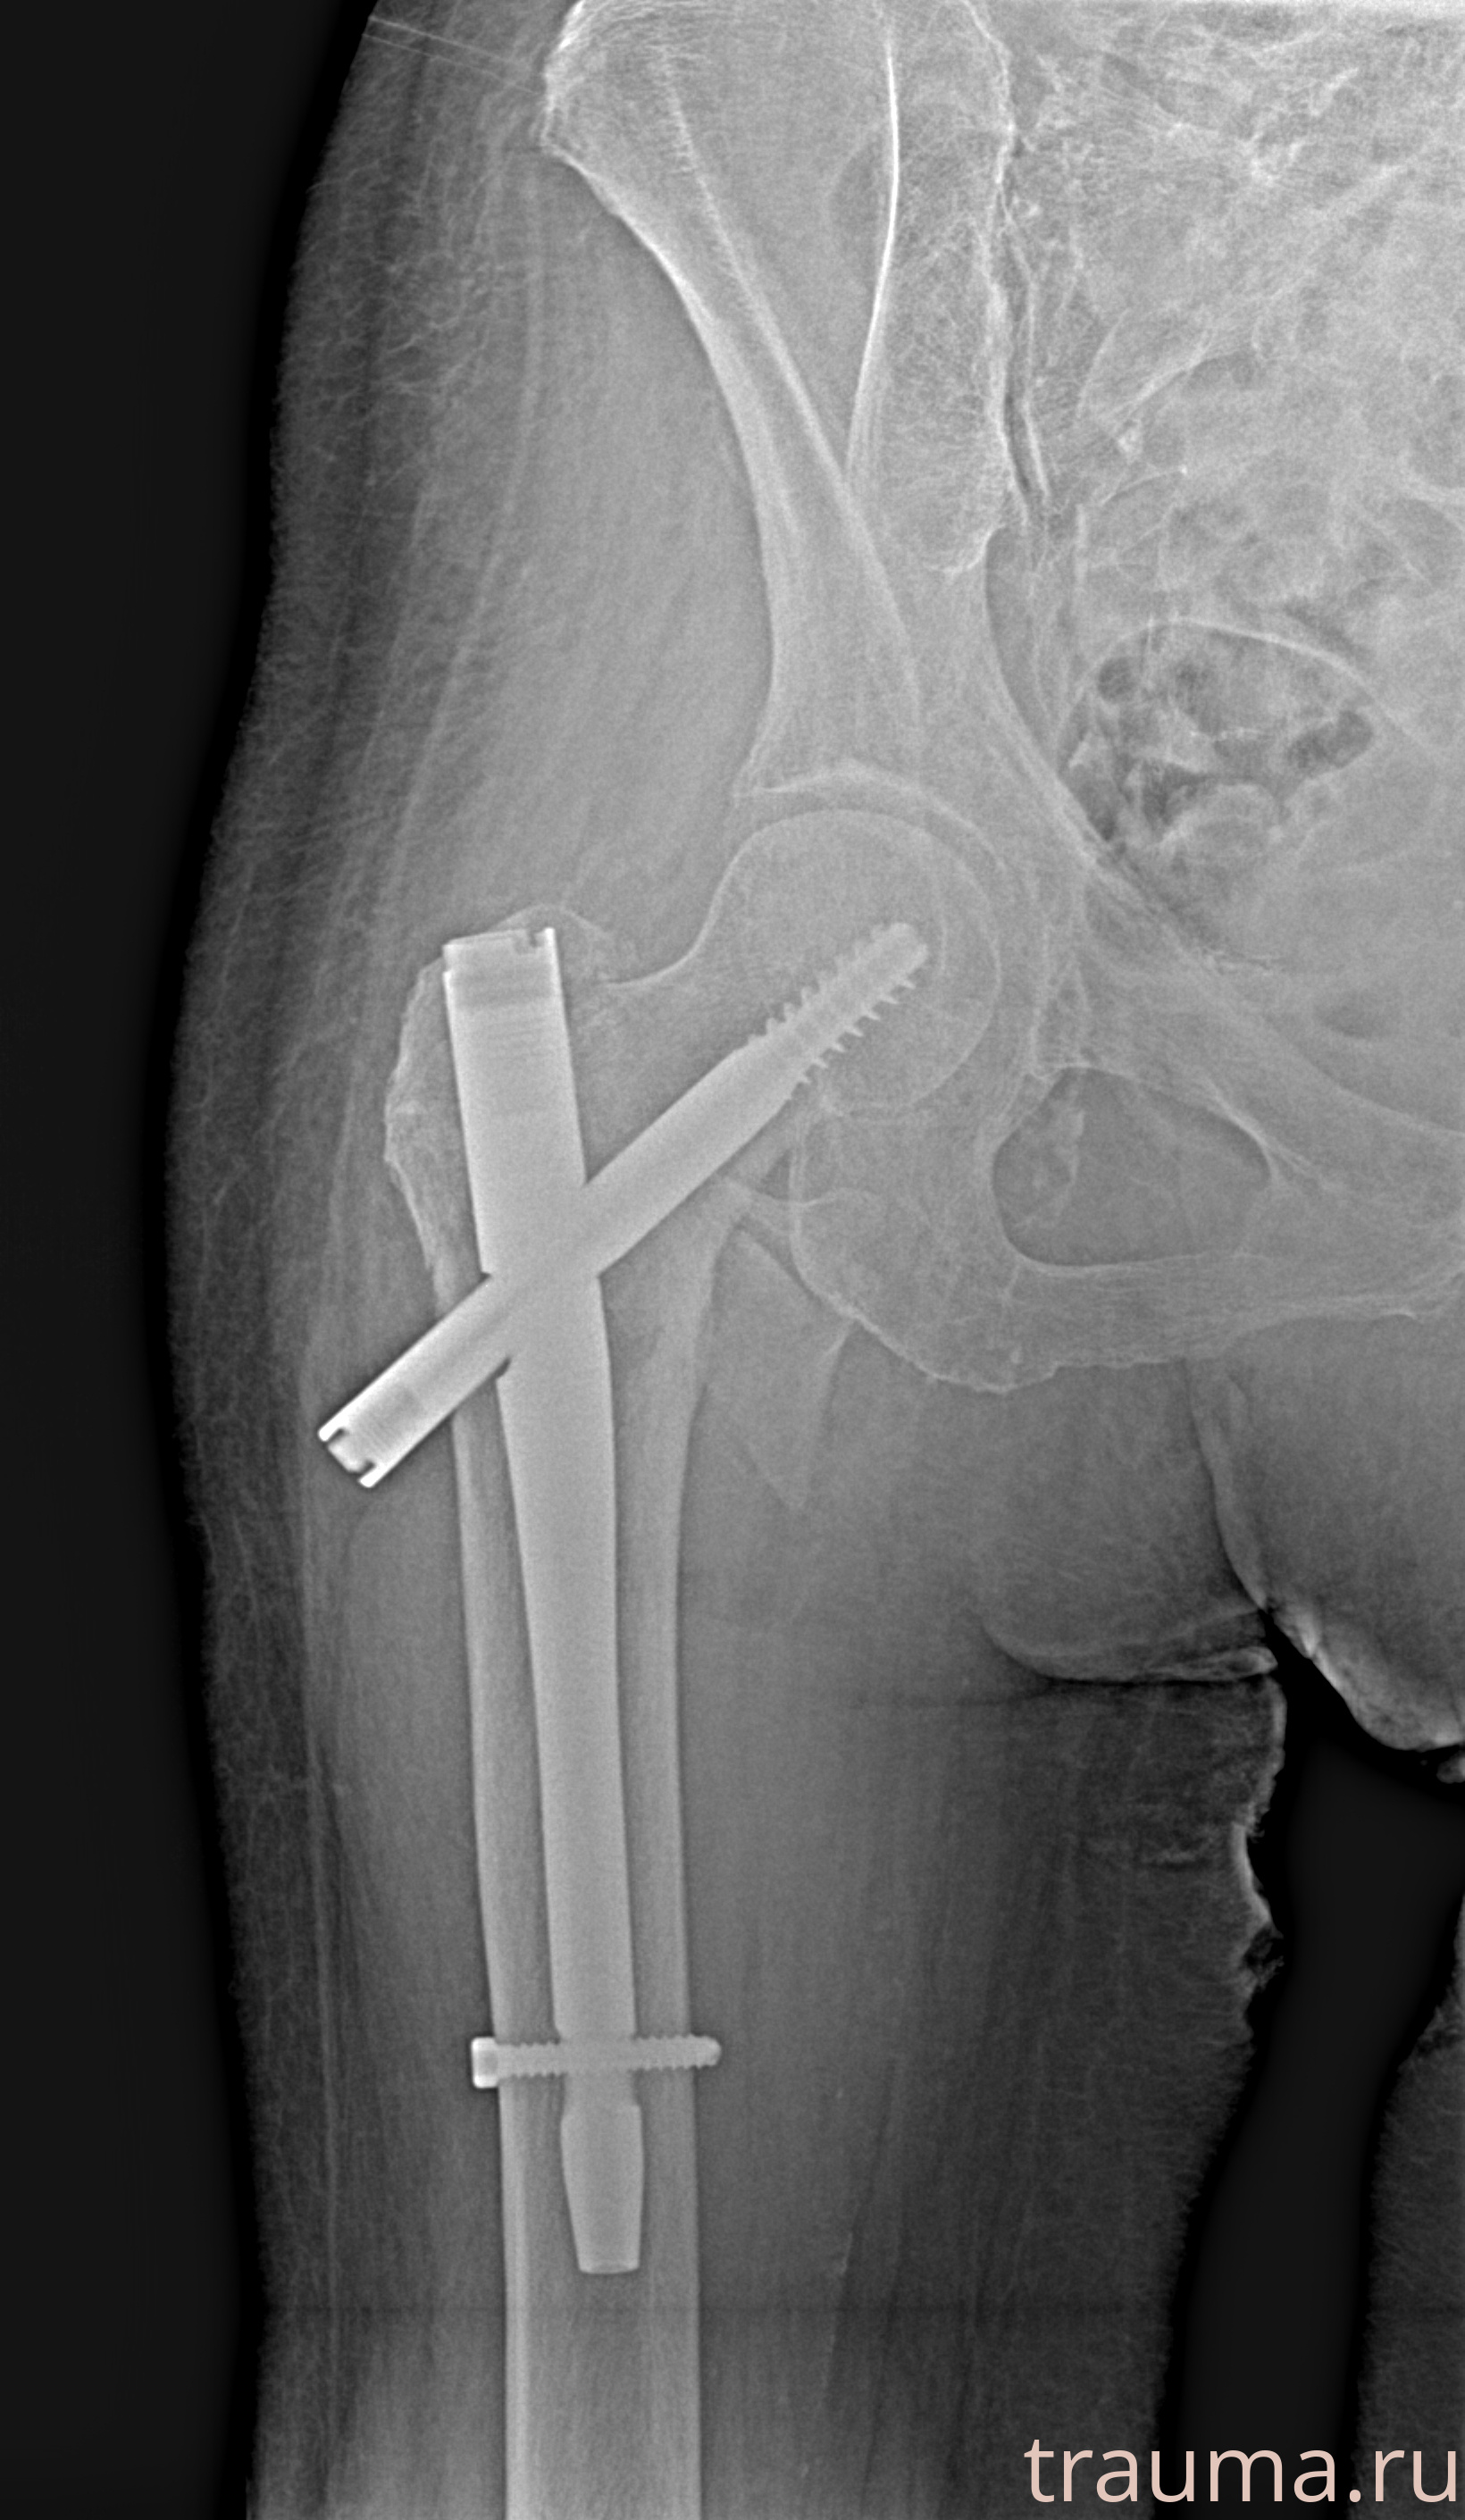

Рентгенограммы

Рентген на дому: по вашему адресу приезжает врач-рентгенолог, травматолог-ортопед с мобильным рентгеновским аппаратом, проводит диагностику травмы или заболевания, делает необходимые рентгенограммы, дает рекомендации по дальнейшему лечению. Получить качественные снимки в домашних условиях возможно благодаря уникальной методике, разработанной МосРентген Центром для института  Склифосовского